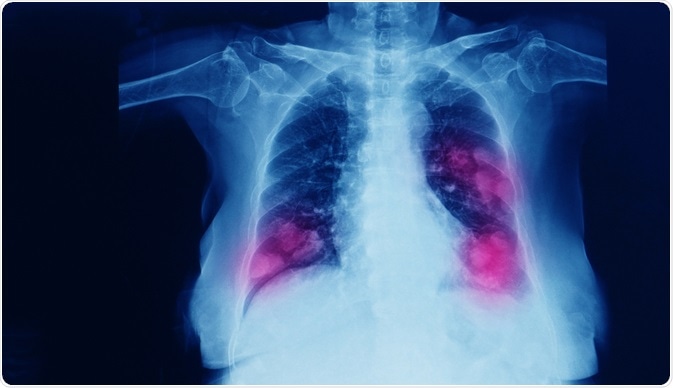

When cancer has started to spread from its original location, it is called metastatic cancer. Metastatic lung cancer denotes a lung cancer that has begun to spread. Metastasis is the process by which cancer cells detach themselves and travel through the body via the bloodstream or lymph system.

The most common places a lung cancer would metastasize to are the brain, bones, and adrenal glands. On the other hand, the most common types of cancer tumors that metastasize to the lungs are breast, colon, prostate, and bladder cancer, neuroblastoma, sarcoma, and Wilm’s tumor. While these are the most common ones, almost any cancer is capable of spreading to the lungs.